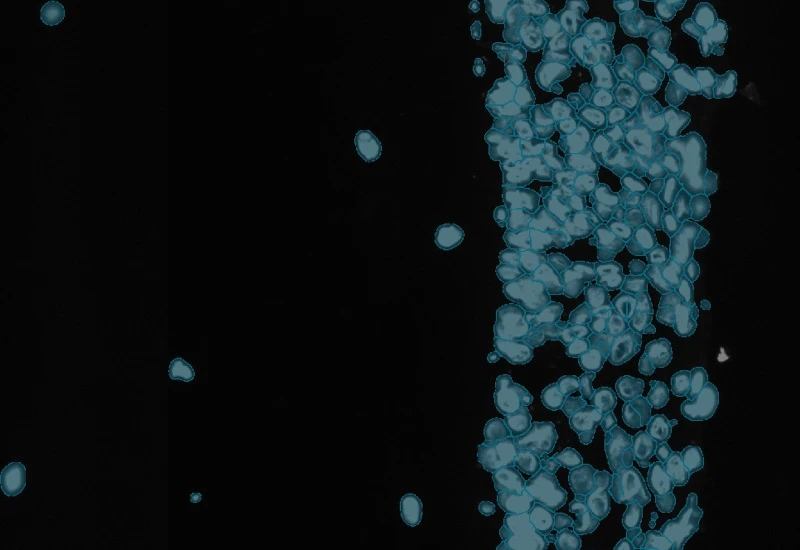

The IF Artificial Skin App stratifies skin equivalents into differnet layers including dermis and epidermis and identifies nuclei based on appropriate staining. Further is subclassifies epidermis into stratum corneum, high suprabasal, low suprabasal, basal. The App outputs, area (µm2) of epidemis and dermis, area and mean staining intensity for each sublayer of the epidermis, total number of nuclei for each layer/sublayer and number/% of marker positive cells for each layser and sublayer.

Image courtesy of Prof. Florian Gruber